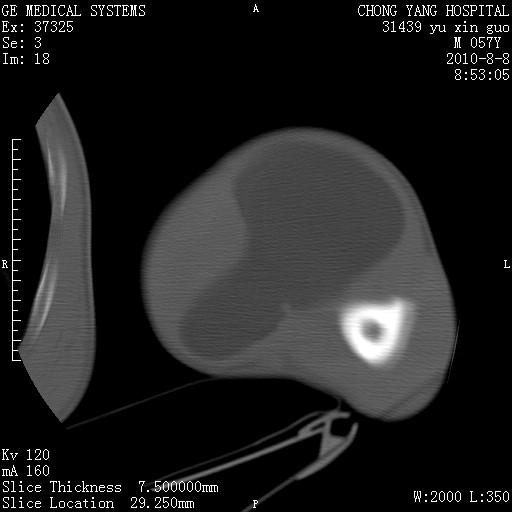

标题: CT28267:M57Y 上臂包块8年余。 [打印本页]

标题: CT28267:M57Y 上臂包块8年余。

包膜光滑、完整的脂肪密度肿块,支持脂肪瘤。